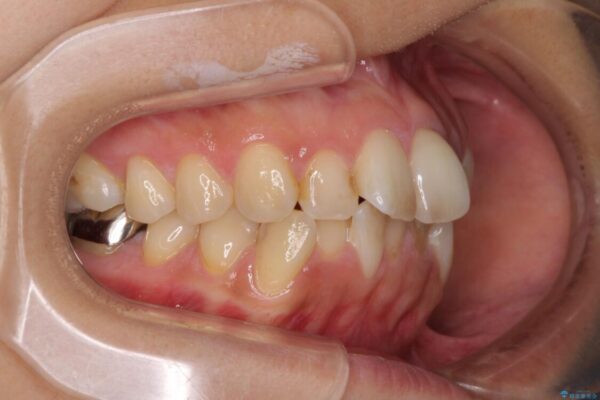

治療後

• デコボコと口元の突出感 ハーフリンガルでの抜歯矯正 治療後画像